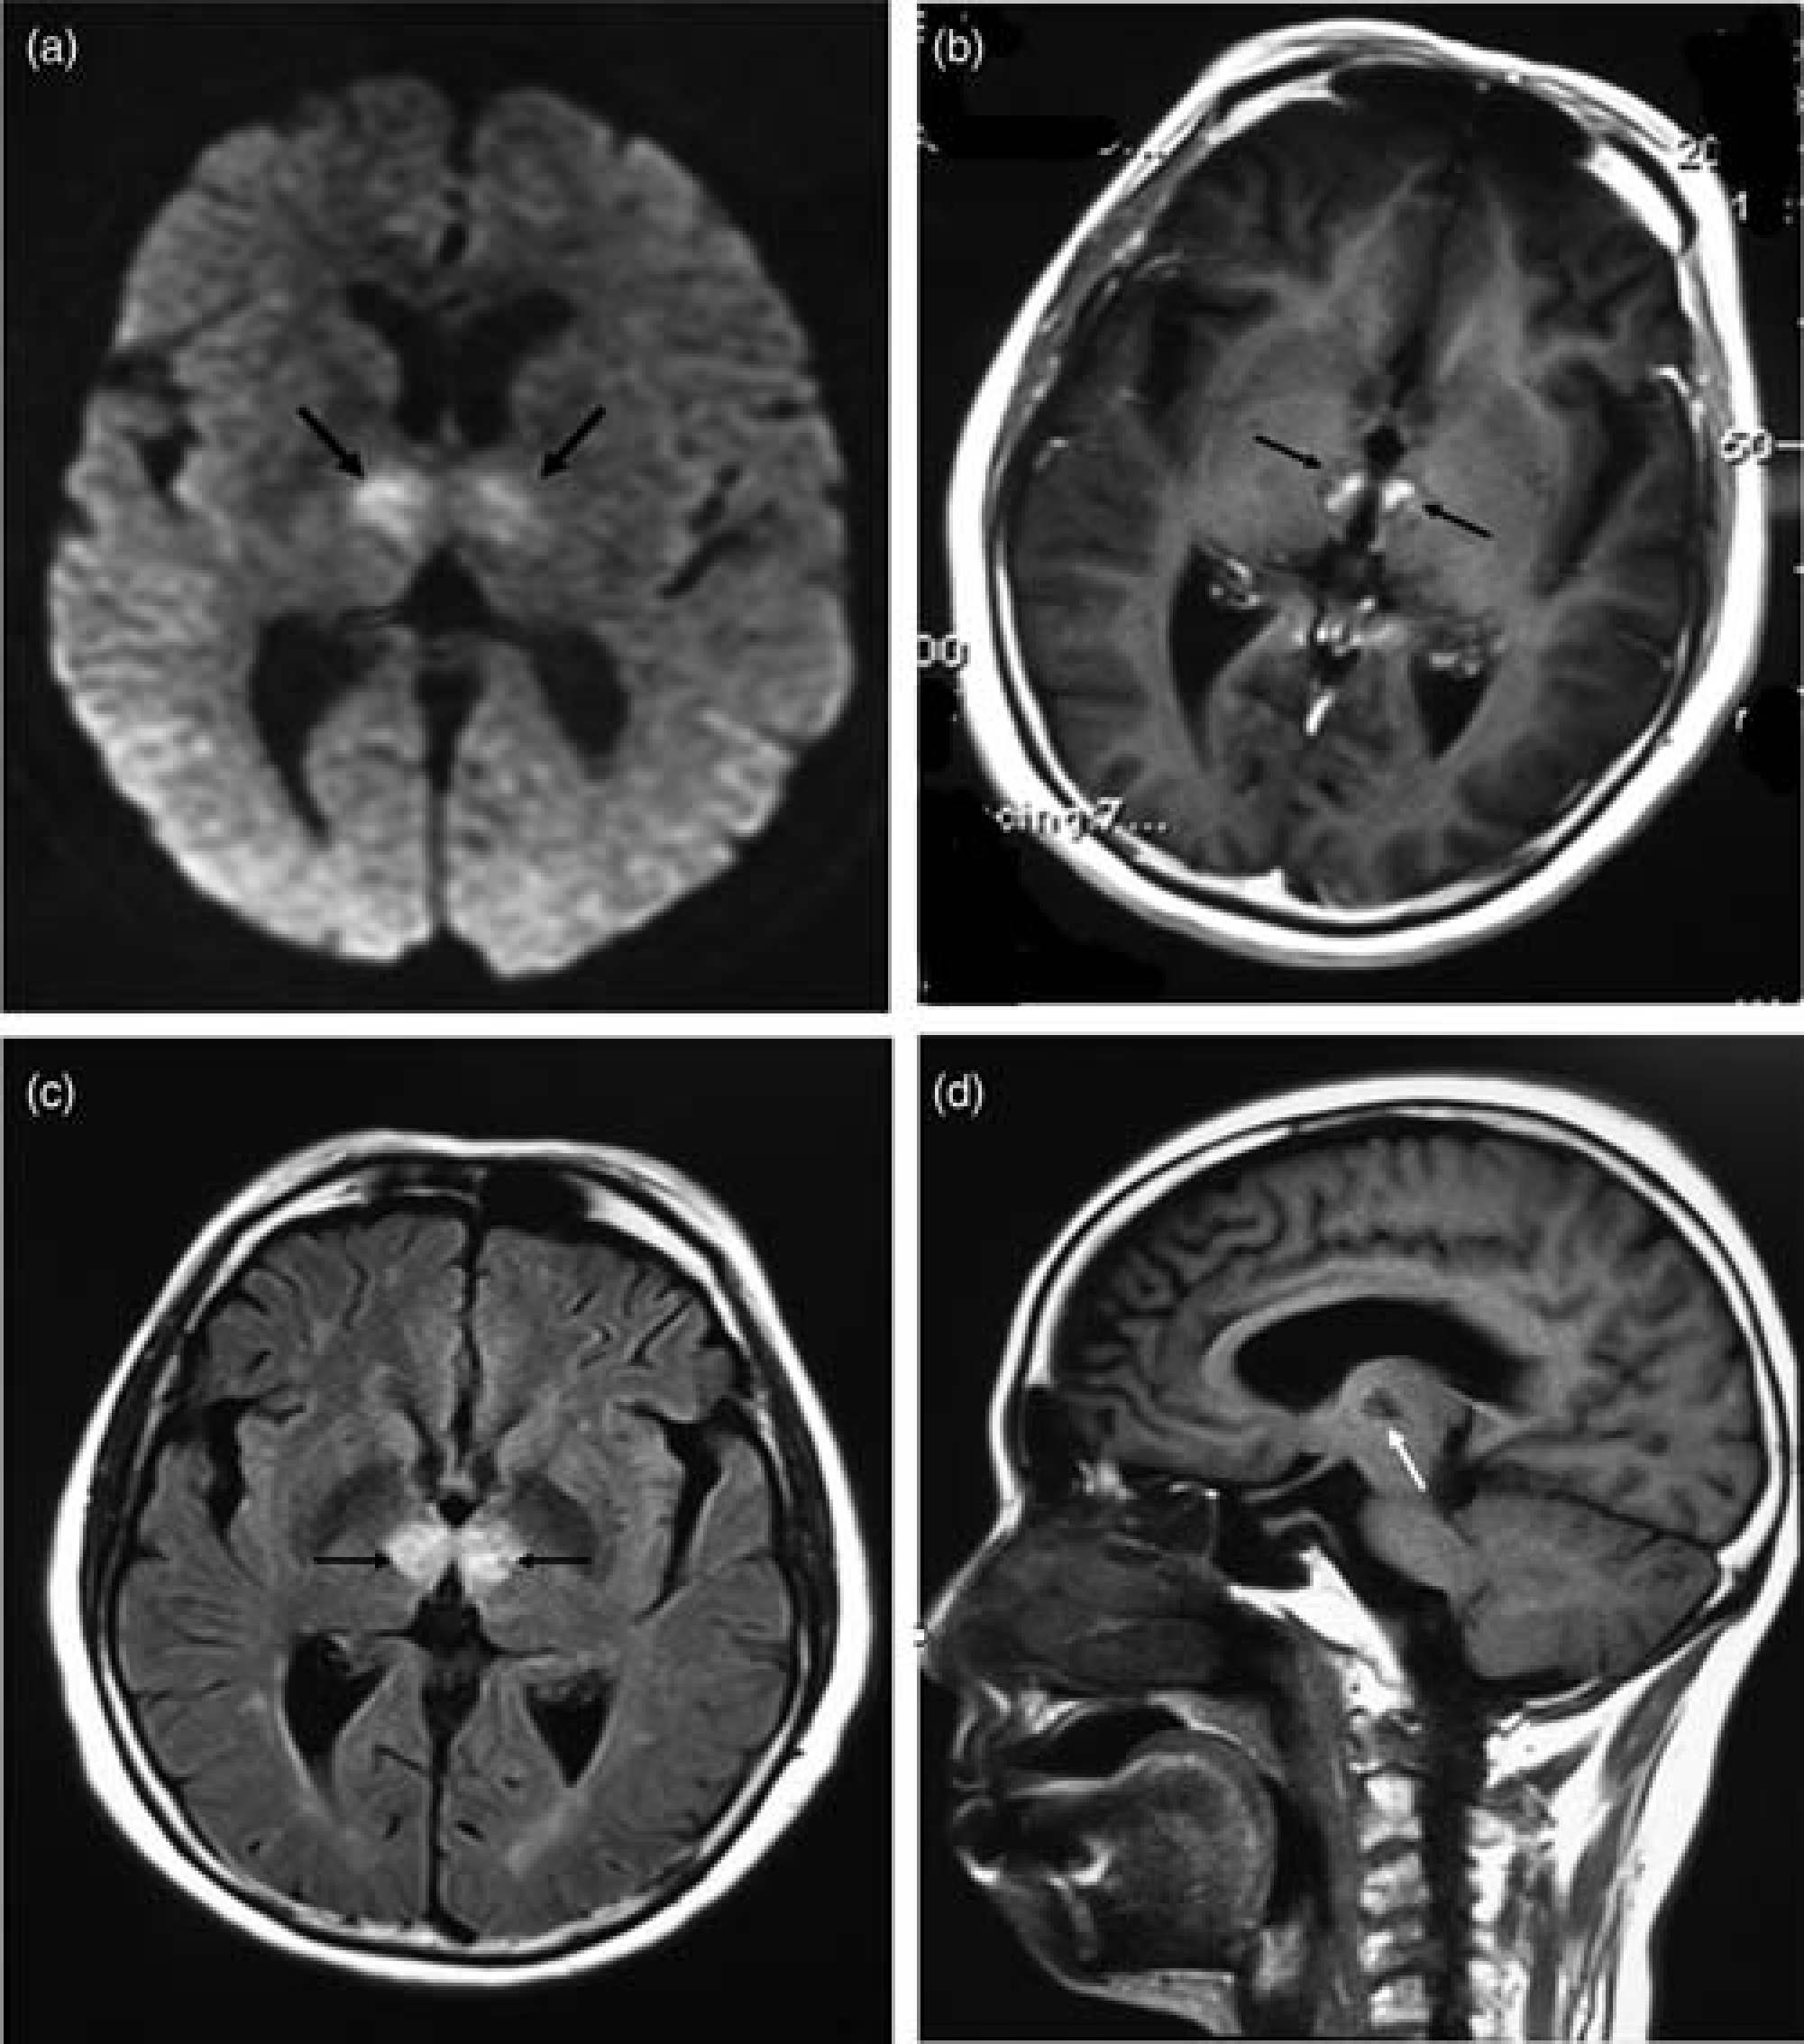

A 61-year-old woman was admitted to the emergency room with sudden onset of unconsciousness. CT showed no acute hemorrhage or infarctions. She received thrombolysis (rt-PA) within 6 h and Glasgow Coma Scale (GCS) score was back to 15 right after. However, she still complained of drowsiness and mild memory deficit. Diffusion-weighted imaging (DWI) the next day showed symmetrical paramedian thalamic high signal intensity (Fig. 1). The patient was then transferred to our hospital after 20 days. On admission she was somnolent and disoriented to time and place. Neurological examination showed vertical gaze palsy and upgoing plantar reflexes bilaterally.

(a) Axial trace diffusion-weighted image obtained 24 h after the onset of symptoms showed bilateral thalamic areas of high signal intensity (black arrows) suggesting acute paramedian thalamic infarcts. (b) Axial T1-weighted post-contrast image obtained after 20 days showed contrast enhancement in the bilateral thalamic infarcts (black arrows). (c) Axial flair-weighted image showed rounded areas (black arrows) of increased signal intensity in the medial thalamus. (d) Lateral T1 -weighted image showed bilateral paramedian thalamic without anterior thalamus and midbrain area of low signal intensity (white arrow)

She had no history of diabetes, hypertension, hyperlipidemia, or atrial fibrillation. Laboratory investigations were unremarkable. An MRI after three weeks showed symmetric enhanced signals in the paramedian thalamus (Fig. 1). Digital subtraction angiography (DSA) showed that the P1 segment of the right PCA was absent. The P2 segment was supplied by the right posterior communicating artery (PcomA). A stenotic AOP originated from the left P1 segment was also visualized (Fig. 2).